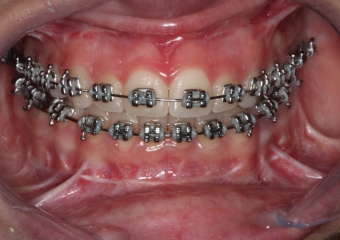

Mordida após a cirurgia